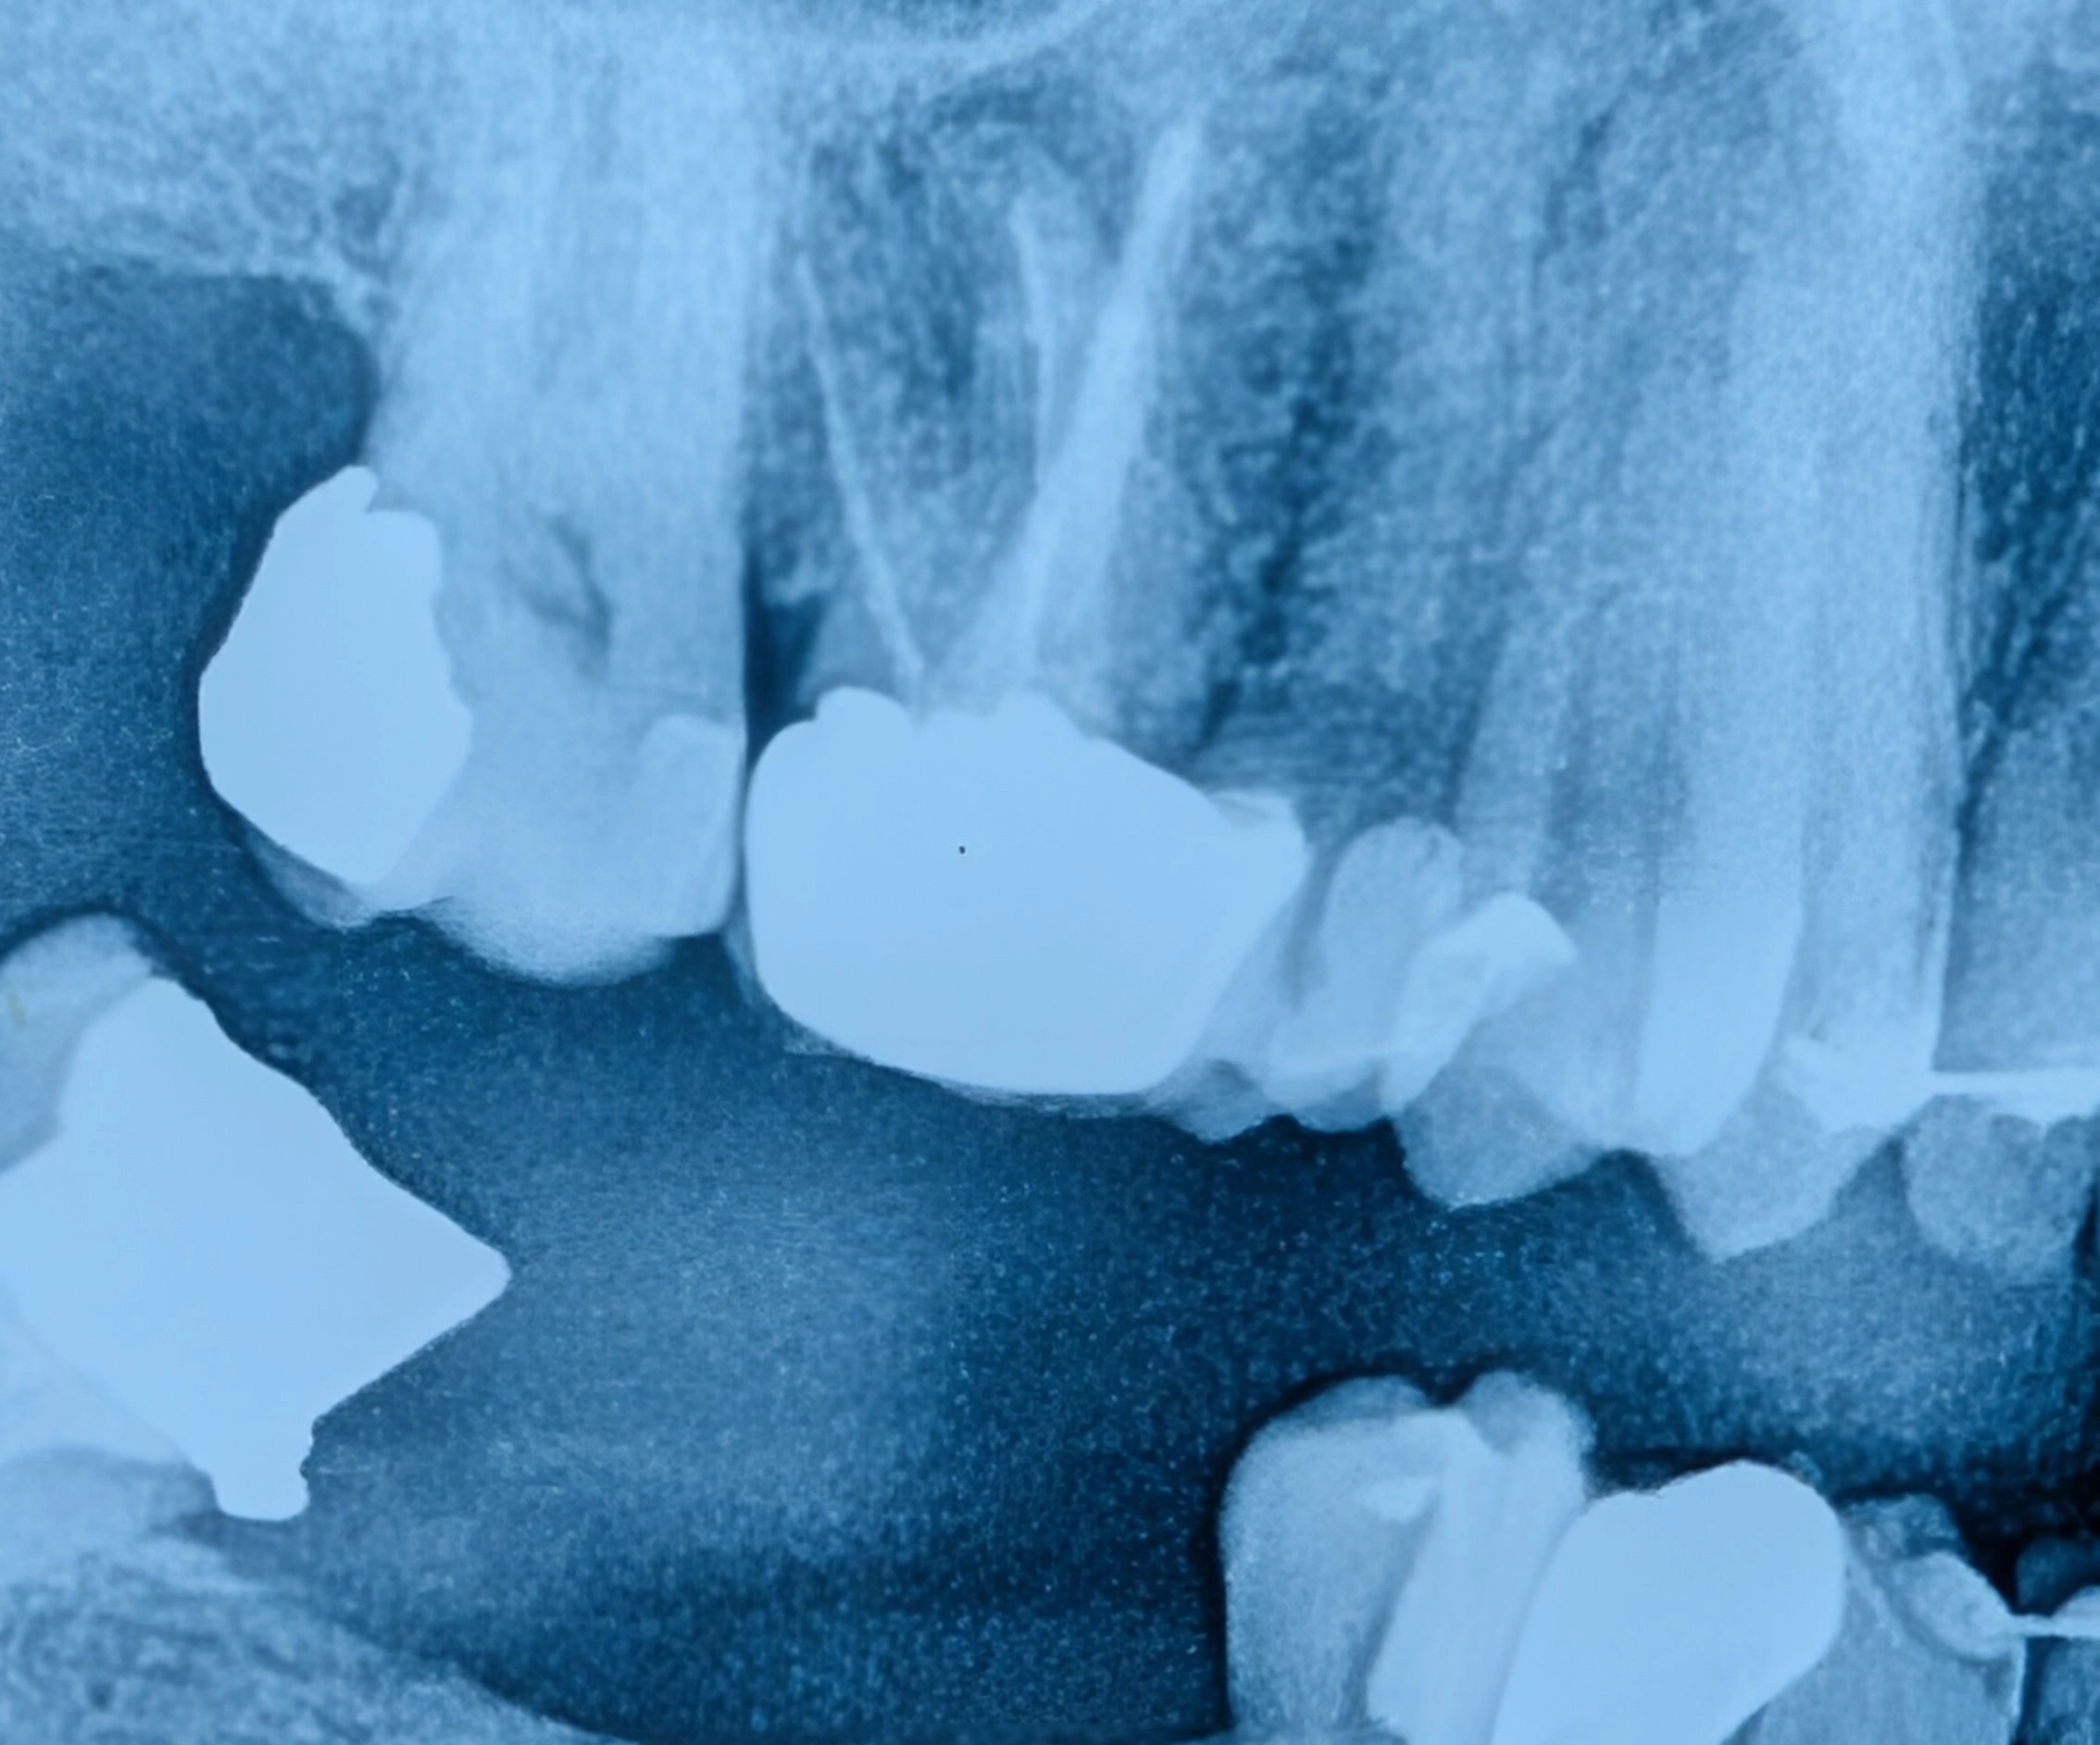

رادیوگرافی PA دندان‌های خلفی

نمای دقیق‌تر دندان‌ها در رادیوگرافی PA

عکس‌های کوچک دندانی مانند PA یا بایت‌وینگ روی چند دندان مشخص تمرکز دارند و جزئیات بسیار دقیق‌تری نشان می‌دهند.

به همین دلیل، این تصاویر بهترین روش برای تشخیص پوسیدگی‌های بین دندانی و بررسی مشکلات ریشه دندان محسوب می‌شوند.

نمونه مقایسه در این بیمار

در تصاویر مربوط به دندان‌های ۴، ۵ و ۶ فک بالا، در عکس پانورامیک ناحیه بین دندان‌ها واضح دیده نمی‌شود، اما در تصویر PA همان ناحیه با جزئیات بیشتر قابل مشاهده است و تشخیص پوسیدگی با دقت بالاتری انجام می‌شود.